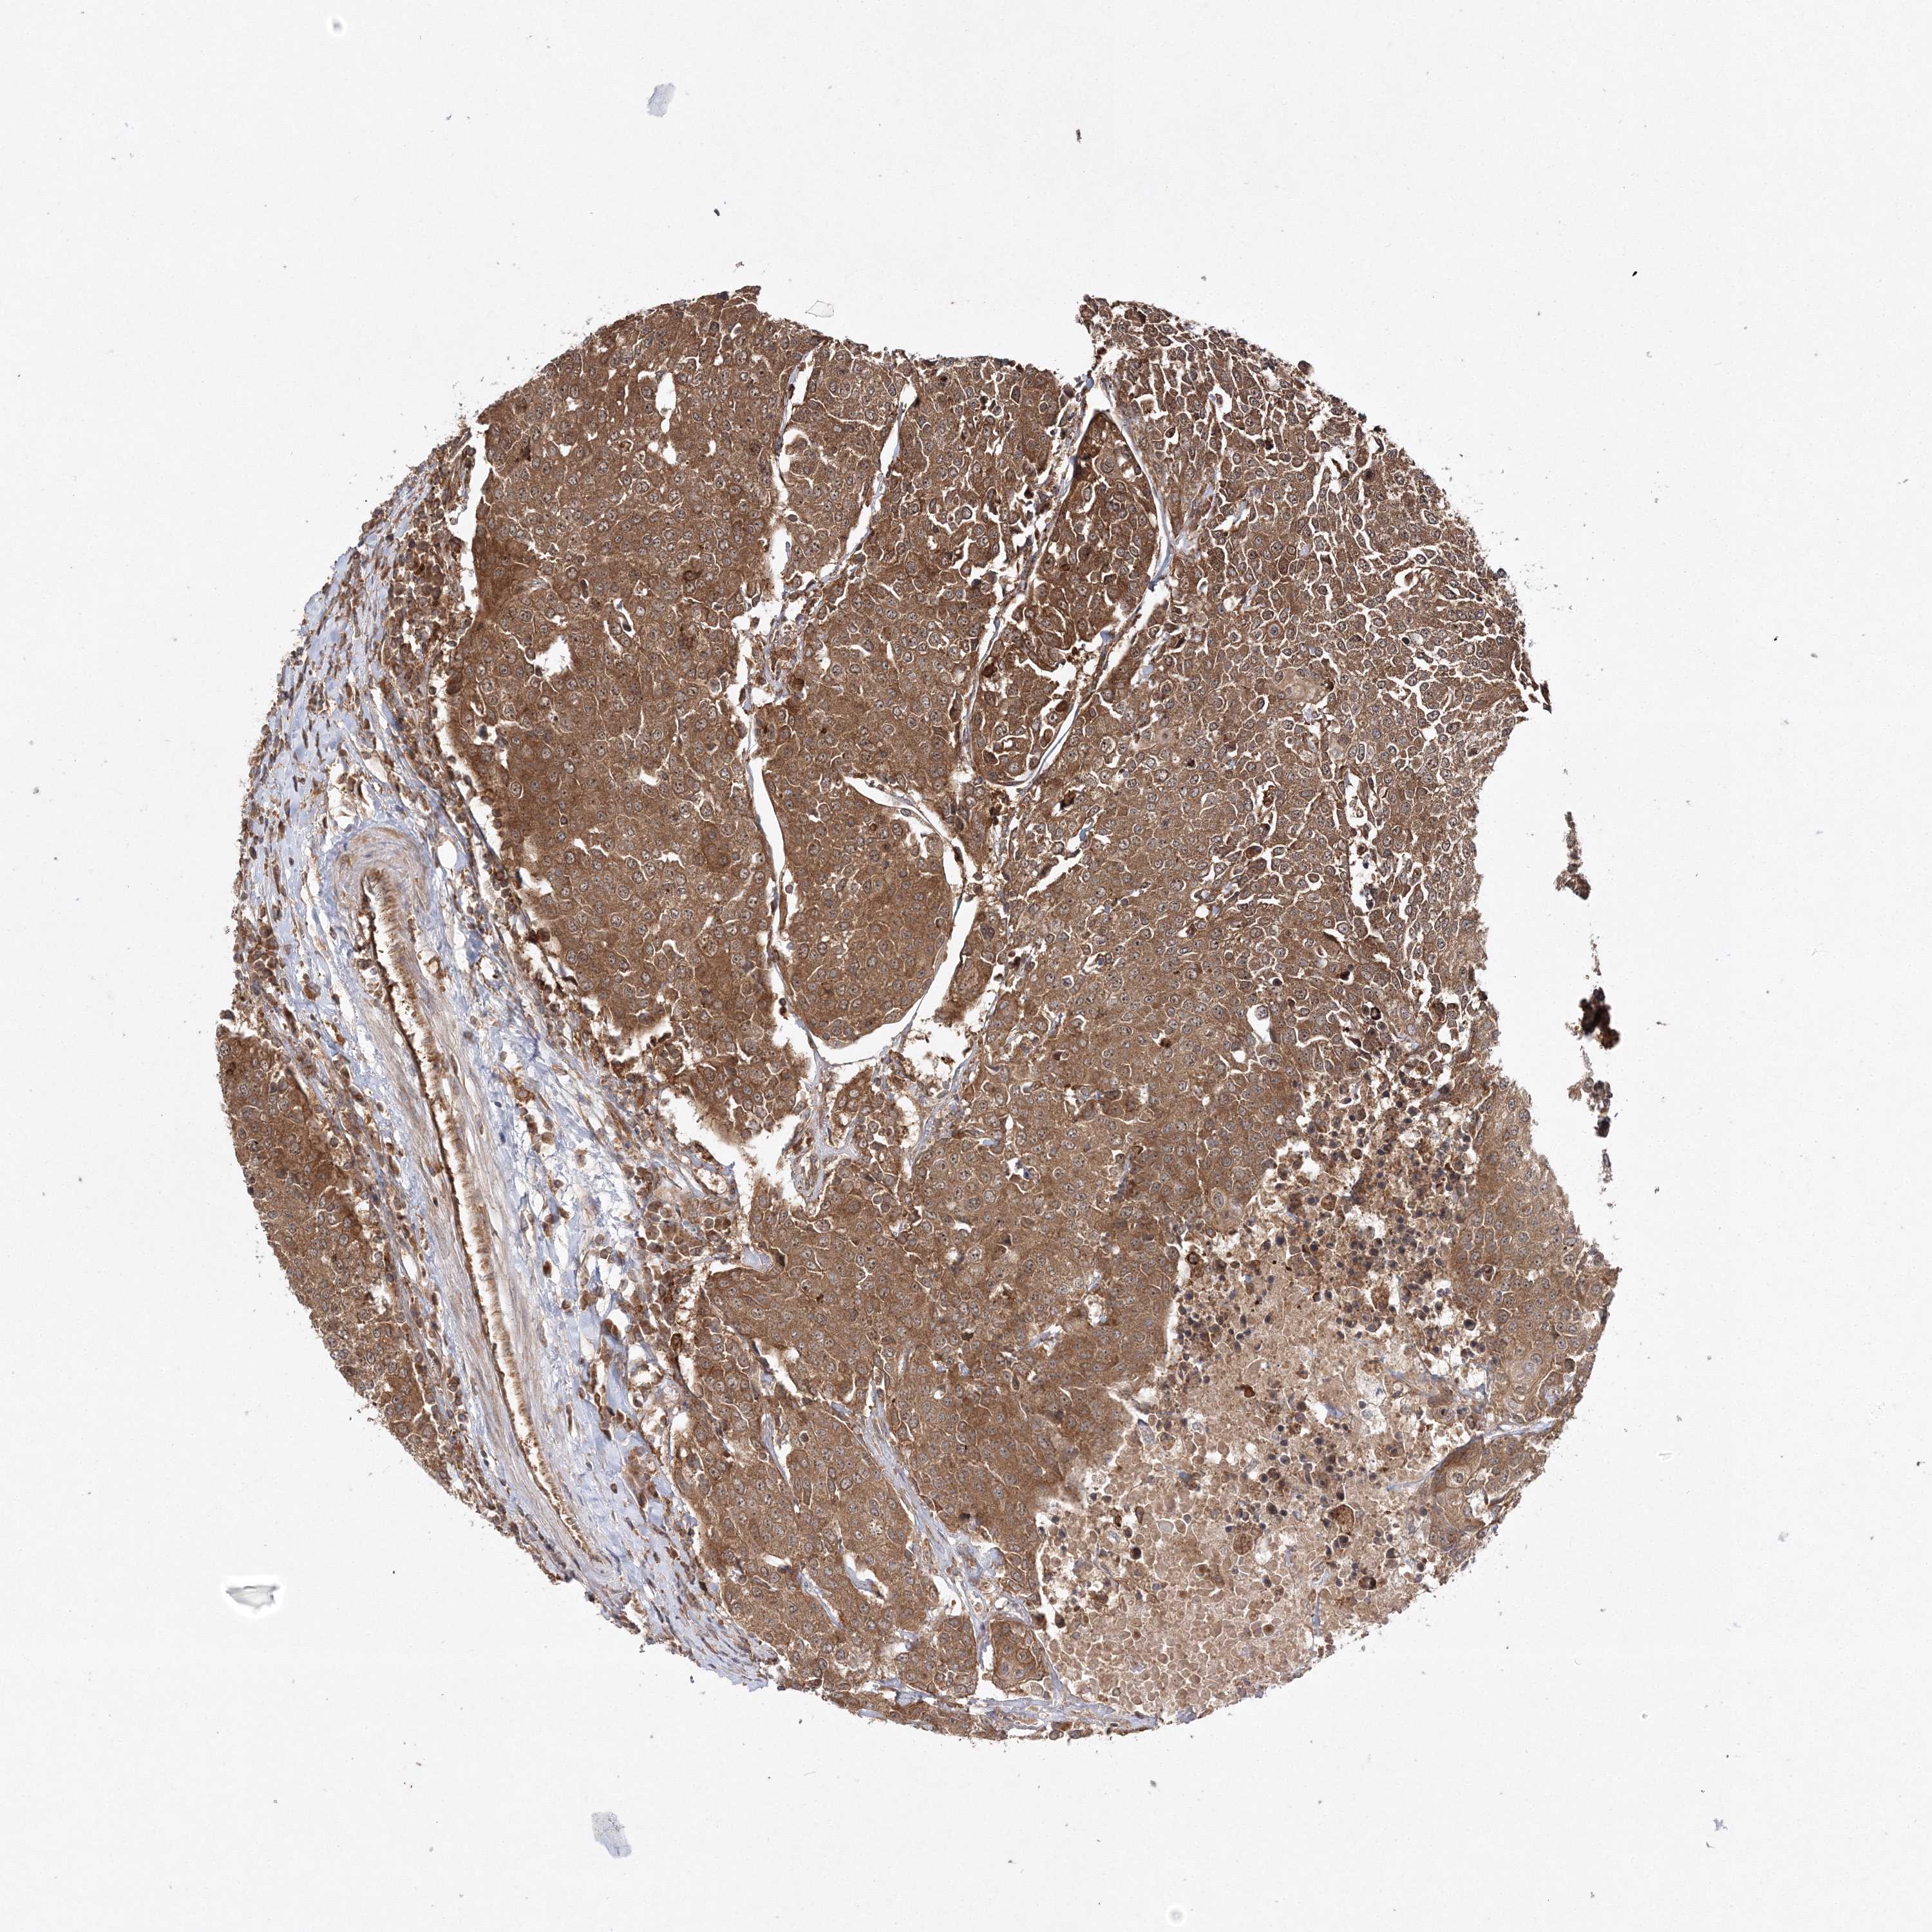

UROTHELIAL CANCER - Protein expressioni

A mouse-over function shows sample information and annotation data. Click on an image to view it in a full screen mode. Samples can be filtered based on level of antibody staining by selecting one or several of the following categories: high, medium, low and not detected. The assay and annotation is described here.

Antibody stainingi

Antibody staining in the annotated cell types in the current human tissue is reported as not detected, low, medium, or high, based on conventional immunohistochemistry profiling in selected tissues. This score is based on the combination of the staining intensity and fraction of stained cells.

Each image is clickable and will lead to virtual microscopy that enables deeper exploration of all samples and also displays staining intensity scores, fraction scores and subcellular localization as well as patient and tissue information for each sample.

Antibody HPA037376

Antibody HPA037565

Staining

High

Medium

Low

Not detected

Intensity

Strong

Moderate

Weak

Negative

Quantity

>75%

75%-25%

<25%

None

Location

Nuclear

Cytoplasmic/membranous

Cytoplasmic/membranous,nuclear

Urothelial carcinoma, Low grade

Urothelial carcinoma, High grade